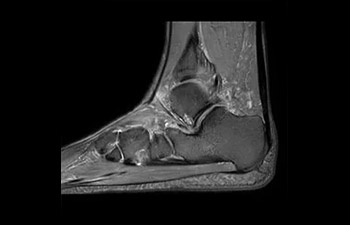

• Es una innovadora técnica de aceleración que no solo permite agilizar las secuencias, sino todo el estudio. • Implementación especial con la que las exploraciones en 2D y 3D pueden llegar a ser hasta un 50% más rápidas con una calidad de imagen prácticamente equivalente.1

• Se puede usar con todos los contrastes y con todas las regiones anatomías.

con Compressed SENSE